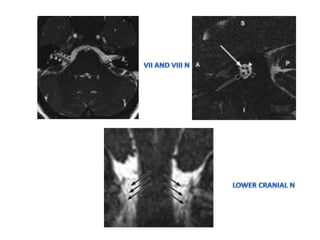

• CISS / 3D FIESTA(fast imaging employing steady-

CRANIAL NERVES IMAGING